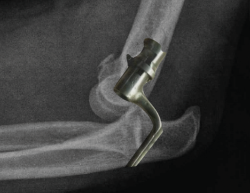

Figura 16. Fractura luxación transolecraneana de codo tratada quirúrgicamente mediante la reducción abierta anatómica y fijación interna con placa preconformada de cúbito proximal.

Las placas preconformadas de cúbito proximal son de elección en este tipo de fractura(37,38,39,40). Esto es debido a que nos permiten realizar una reducción anatómica de todos los fragmentos y restablecer tanto la anatomía de la fosa sigmoidea mayor como de la coronoides. En ocasiones, puede ser necesario el uso de injerto óseo para la reconstrucción de la fosa sigmoidea mayor, dado que estas fracturas suelen ser consecuencia de impactos de alta energía y puede encontrarse mucha conminución del foco de fractura(41). Los errores más comunes durante el manejo quirúrgico de estas fracturas-luxaciones son(42):